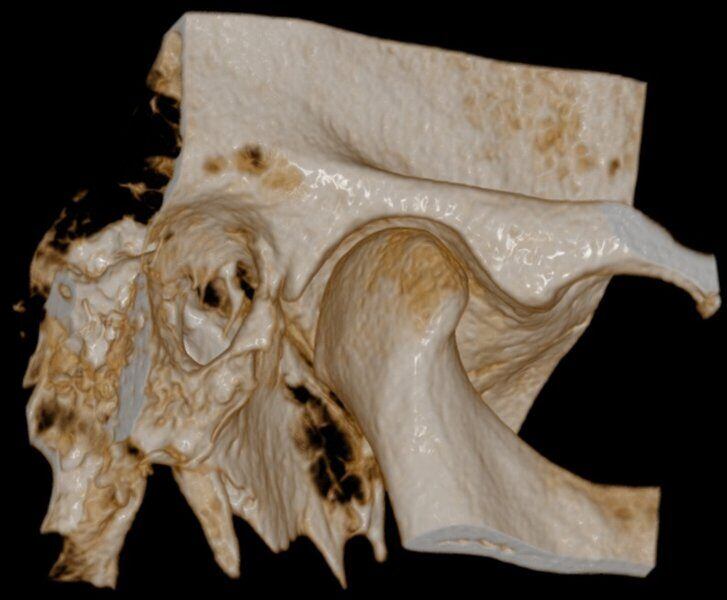

Acquisizione Maxiillofacciale per valutazione chirurgica di paziente con Sindrome di Goldenhar